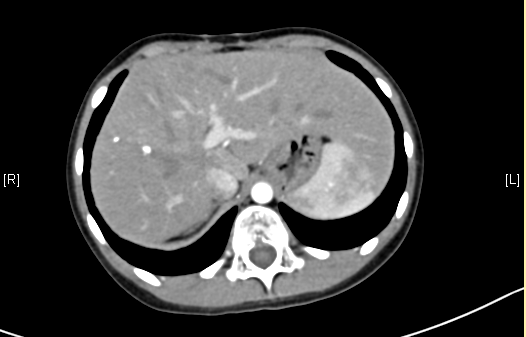

术前CT检查:

动脉期

一般情况:CH-001-LT-000009,男,7岁,身高128cm,体重24.5kg。

现病史:因感冒后出现上腹部不适,至当地医院就诊,查腹部超声示“肝脏占位”,遂至青岛妇女儿童医院就诊,查腹部CT示“肝脏占位”,未予特殊治疗,为求进一步诊治来我院就诊,门诊以"肝脏占位"收入院。

腹部超声示:肝内包块。腹部CT:肝脏占位,血管瘤?上腹部增强CT:肝左内叶-右前叶交界区、尾叶囊实性团块影,考虑肿瘤(胆管囊腺瘤?间叶性错构瘤?)